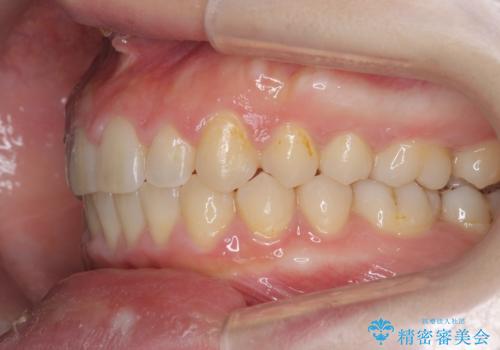

深い噛み合わせ、すきっ歯の改善 ワイヤーを用いたマルチブラケット矯正

- 噛み合わせが深く、前歯が突き出て隙間が出てきたことの改善を希望され矯正治療の相談で当院に初診来院されました。

ワイヤーを用いたマルチブラケット矯正を行うことで深い噛み合わせを改善し、前歯の隙間もなくし審美的な歯列へと治療をおこなっていきます。